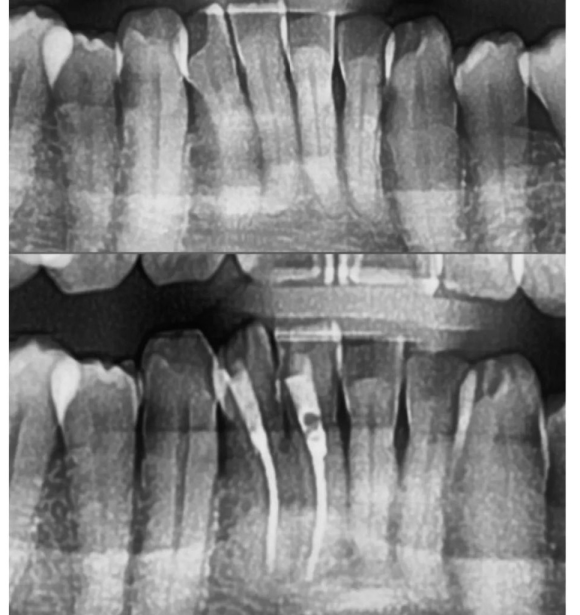

2022.4.13 시린니치아 당일발수근충마무리 후 레진core. 근관 shaping이 매우 어려웠던 케이스 리더스진치과는 보존보철 과장님과 함께 협진으로 많은 진료를 원칙적으로 하고 있습니다.

2022.4.13 시린니치아 당일발수근충마무리 후 레진core. 근관 shaping이 매우 어려웠던 케이스

리더스진치과는 보존보철 과장님과 함께 협진으로 많은 진료를 원칙적으로 하고 있습니다.